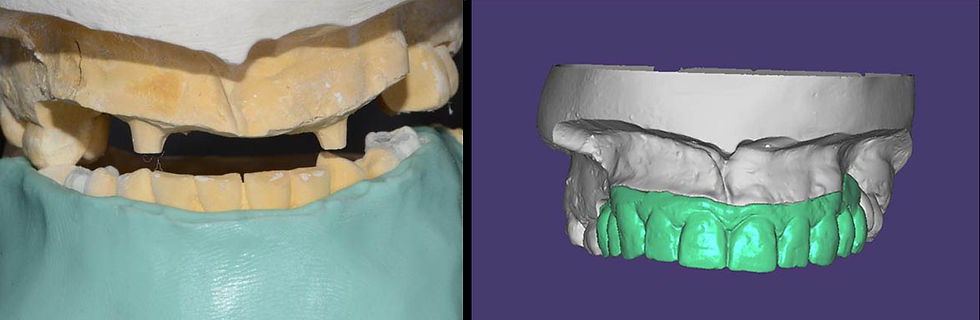

The first wax-up is then scanned, and the cast is discarded up to the mark made at the smile line (aesthetic area).

A new scan is then acquired to create the temporary file that will be milled in PMMA.

PMMA temporary prosthesis obtained with CAD-CAM technology.

On the temporary prosthesis it is possible to remove material in the area of the prosthetic flange and fill with palate resin for mobile prosthesis.